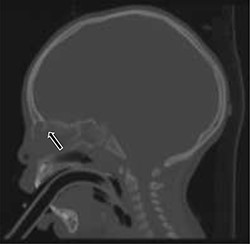

A total of fourteen patients were identified. The age range of these patients was 6 months to 17 years. There was an equal gender distribution. An average of 11 weeks lapsed between initial presentation and definitive excision. All patients underwent MRI; all patients exhibited an abnormality, most commonly isointense T1 and hyperintense T2 soft tissue findings in the area of the nasal dorsum/glabella (Fig. 2). Eleven of the fourteen patients (78.6%) underwent a CT. Of those eleven patients, two patients exhibited a splaying of nasal bones (Fig. 3). Fifty percent of the patients required preoperative antibiotics for infected nasal dermoid cysts; one patient was admitted to the infectious disease service for intravenous antibiotic therapy prior to formal surgical excision. One of the fourteen patients (7.1%) had a formal excision with a rhinoplasty approach, while the majority thirteen of the fourteen patients (92.8%) underwent an open vertical incision for the surgical approach. Four of the fourteen patients (28.5%) had recurrent infection and required additional surgery. Three of seven patients required incision and drainage prior to definitive excision. One of seven patients in the infected group had recurrence. Three of the seven patients in the non-infected group recurred. Bacterial cultures in all of these patients did not identify common pathogens. Surgical pathology revealed acute on chronic inflammation in 50% of cases; three of the fourteen patients (21.4%) revealed multinucleated giant cells on microscopic analysis. Two of the fourteen total patients had intracranial extension. None of these patients developed meningitis.

Sagittal cranial CT scan with bone window showing splaying of the nasal bone; a severe osseous defect potentiating extension into the intracranial space.